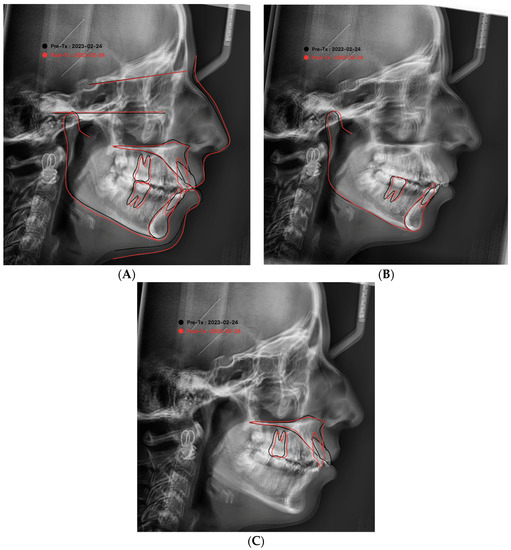

2.4. Cephalometric Analysis